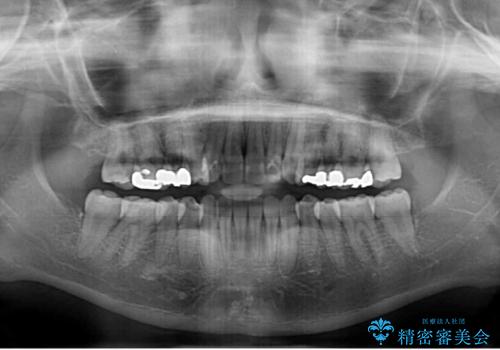

- 中学生の時に矯正治療をしたものの、後戻りを気にして来院された患者様です。

骨格的に下顎が右側に変位しているため、左右の咬み合わせを理想的なものに改善することはできませんが、インビザラインにて歯列を整えることとしました。

骨格的なズレによる左右差は改善できませんでしたが、上下の正中を極力合わせるようにすることができました。